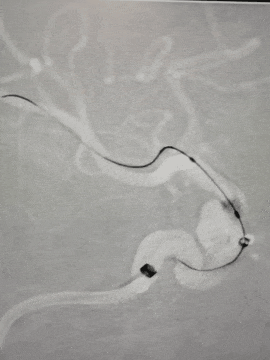

右侧颈内动脉:

Synchro 2导丝和XT-27同轴带CAT5到大脑中M1段远端

路径迂曲,海绵窦III型导致基础支撑不足,长鞘下坠,Surpass Streamline血流导向密网支架无法到位。

Infinity长鞘轻松推送至海绵窦段高到位,微导丝和CAT 5送高,增强系统支撑,支架顺利到位。